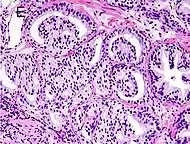

Gleason pattern 4. H&E stain.

• Pattern 4 - The tissue has few recognizable glands. Many cells are invading the surrounding tissue in neoplastic clumps. This corresponds to a poorly differentiated carcinoma.

Gleason 4

Gleason pattern 4 glands are no longer single/separated glands like those seen in patterns 1-3. They look fused together, difficult to distinguish, with rare lumen formation vs Gleason 1-3 which usually all have open lumens (spaces) within the glands, or can be cribriform-(resembling the cribriform plate/similar to a sieve: an item with many perforations). Fused glands are chains, nests, or groups of glands that are no longer entirely separated by stroma-(connective tissue that normally separates individual glands in this case). Fused glands contain occasional stroma giving the appearance of "partial" separation of the glands. Due to this partial separation, fused glands sometimes have a scalloped (think looking at a slice of bread with bite taken out of it) appearance at their edges.[4][7]